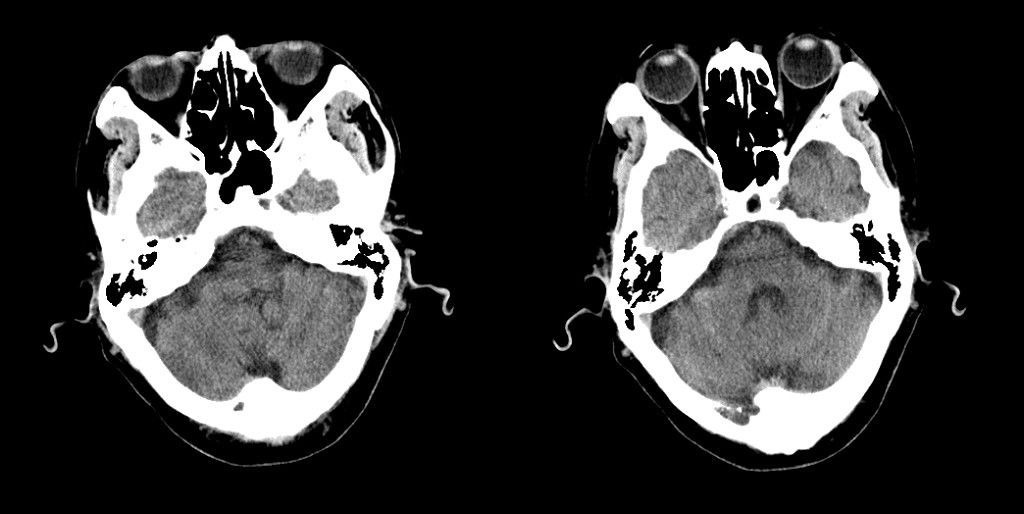

标题: CT25311:箭头所指是问题么?

该患者因头疼来诊,发现枕骨不规则缺损。

箭头所指为颅骨嗜酸性肉芽肿

蛛网膜颗粒压迹,讨论过很多了,年龄大了不考虑lch;脑白质疏松。

箭头所指:蛛网膜颗粒压迹。